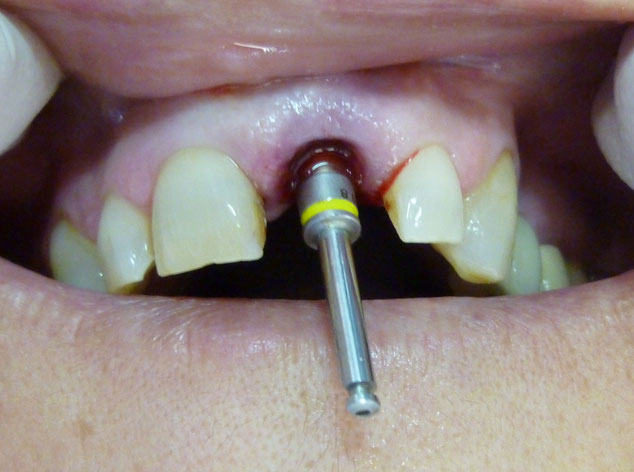

En estos casos han sido tratados con la filosofía de all-at-once, en la

misma sesión: